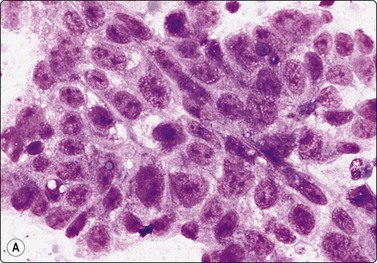

Embryonal carcinoma (Figs 13.33 and 13.34)14,58-61,63,65,66

image image

Fig. 13.33 Embryonal carcinoma

(A) Adenocarcinoma-like tissue fragment of large malignant cells with large vesicular nuclei, coarse chromatin, prominent nucleoli; prominent cytoplasmic vacuolation (MGG, HP); (B) Fragment of undifferentiated mesenchymal tissue right; cluster of malignant epithelial cells with large vesicular nuclei and prominent large nucleoli (H&E, HP) left.

image

Fig.13.34 Embryonal carcinoma

Tissue section corresponding to Fig. 13.33B (H&E, IP).

Criteria for diagnosis

Cell-rich smears,

Frequent three-dimensional clusters,

Occasional tendency to acinar and microglandular grouping,

Large vesicular, obviously malignant nuclei, large nucleoli,

Indistinct cell borders,

Basophilic to amphophilic, sometimes pale, vacuolated cytoplasm,

Immunocytochemistry: cells positive for PLAP, OCT 3/4, CD30, AE1/AE3 and CK7.

The vesicular nuclei of embryonal carcinoma are larger and more pleomorphic than those of seminoma, the chromatin is coarse and irregular and nucleoli are large, occasionally huge, and eosinophilic. The cytoplasm is pale and distinctly vacuolated, but not ‘bubbly’. It is not highly fragile and a TB as in seminoma is not seen. Cytoplasmic boundaries are poorly defined (Fig. 13.33). Hemorrhage and tumor necrosis may be prominent and may hamper the identification of diagnostic cells. It is usually not seen in smears of seminoma. Chromatin threads and reticulated material resembling TB can occur. Large syncytiotrophoblastic cells may be found. Prominent lymphoid/plasma cell infiltrates or mucus are not seen. The presence of cellular mesenchyme on its own does not warrant a designation of teratoma (Figs. 13.33B and 13.34).49